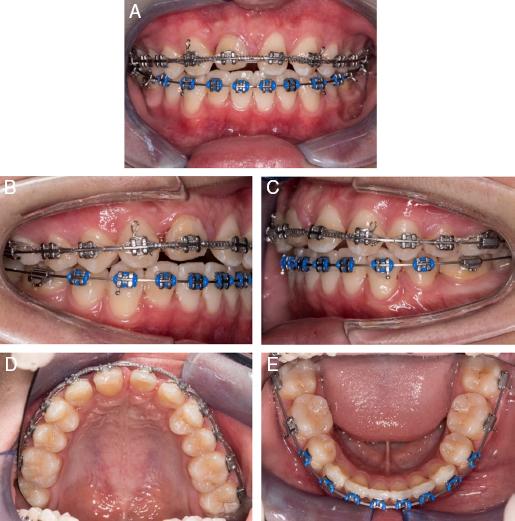

Figure 3.